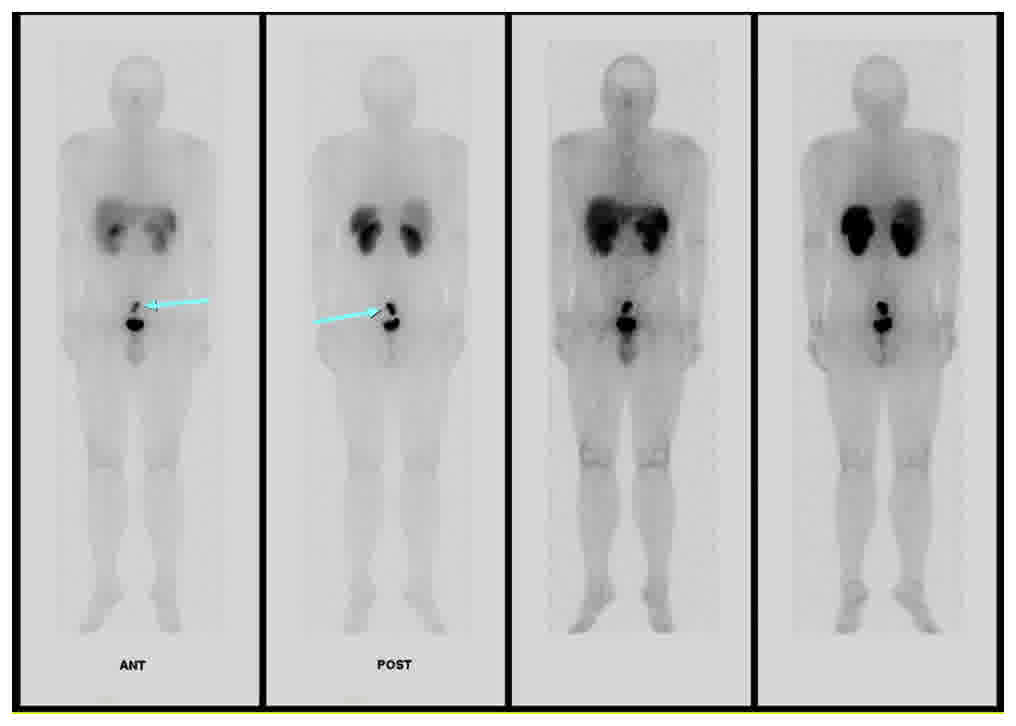

To evaluate the multiple enlarged lymph nodes, Indium-111 octreotide scanning was performed, which indicated an increased uptake of multiple enlarged lymph nodes in the pre-sacral space at the 4 and 24-h delayed scans (Fig. 5). Multiple mesenteric lymph nodes in the right lower quadrant and left para-aortic lymph nodes exhibited no significant abnormal uptake, which suggested a reactive change accompanying acute enteritis.

Figure 5.

Indium-111 octreotide scanning indicating the increased uptake of multiple enlarged lymph nodes in the presacral space (arrow). There was no otherwise definite abnormal increased uptake in the abdomen. ANT, anterior; POST, posterior. The left two panels are images after a 4 h delay, and the right two panels are after a 24 h delay.